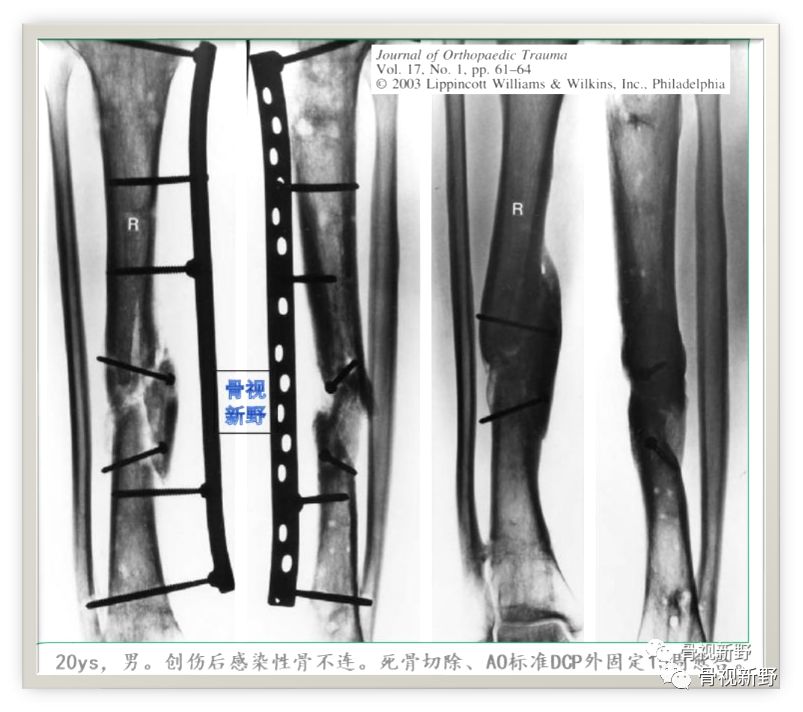

第三次报道

2003年,Rene K.Marti团队再次报道了将AO标准钢板作为外固定架用于开放性骨折以及骨感染性骨不连的固定病例31例,也取得了较好的疗效。

Cases